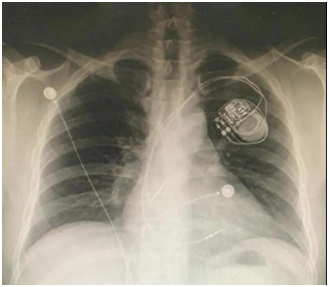

??1.心脏起搏器、ICD(除颤器)

??目前,临床上应用的绝大多数心脏植入式电子设备都不能与MRI兼容。在强磁场中,心脏起搏器、ICD可能会出现装置移位、起搏信号异常、除颤模式异常启动、电极升温等现象,严重时可导致装置损坏、心律失常甚至死亡等后果。

??极少数可兼容的心脏起搏器和ICD,需要在专科医师指导下行MRI检查,需要有说明书并明确注明MRI兼容、安全。

??心脏起搏器